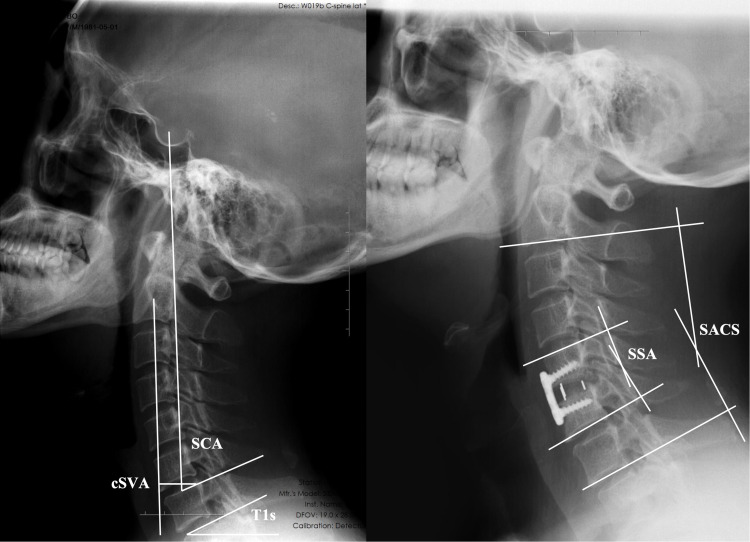

Methods: A total of 98 patients who underwent single-level ACDF with at least 24 months of follow-up were retrospectively analyzed. Radiographic evaluations were conducted preoperatively and at 3, 6, 12, and 24 months postoperatively. Patients were classified into ASD and non-ASD groups based on established radiographic criteria. Pre- and postoperative cervical sagittal parameters, including SCA, T1 slope (T1s), sagittal segmental alignment (SSA), sagittal alignment of the cervical spine (SACS), and C2-C7 sagittal vertical axis (cSVA) were measured. Clinical outcomes were assessed using the Japanese Orthopedic Association (JOA) score, Neck Disability Index (NDI), and Visual Analog Scale (VAS) scores. Multivariate logistic regression and Receiver operating characteristic (ROC) curve analysis were performed to identify independent predictors of ASD.

Results: ASD occurred in 36 patients (36.7%). Preoperative SCA was significantly larger in the ASD group compared to the non-ASD group (86.7° ± 7.4° vs 80.5° ± 6.9°, p < 0.001), while T1s and SSA were significantly smaller (p = 0.015 and p = 0.001, respectively). Multivariate analysis identified preoperative SCA as the only independent risk factor for ASD (OR = 1.279, 95% CI: 1.010-1.619, p = 0.041). Patients with SCA > 84.2° showed a significantly higher incidence of ASD (55.8% vs 21.4%, p < 0.001). ROC analysis demonstrated that SCA had good predictive value for ASD development. No significant differences were observed in JOA, NDI, or VAS scores between the two groups at final follow-up.